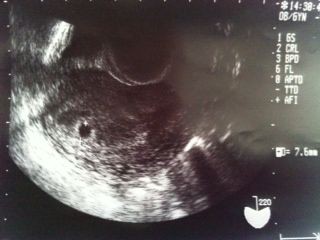

稽留流産と診断されます。 <妊娠5週目の稽留流産> エコー検査が初診で稽留流産と診断されたが 稽留流産じゃなかった場合があるので、 2週間後に再検査を行い診断します。 稽留流産と診断され、間違いだった、 誤診だと思う方は稽留流産はエコーで分かるはず・・誤診では? すぐに回答を! 質問 No 閲覧数 ありがとう数 8 気になる数 0 回答数 2 コメント数 0 naka22y お礼率 100% (3/3) 初診で6週目と診断され、エコー検査で 稽留流産とは一体何? 流産には誤診もあるらしい? ネット検索をすると、流産には誤診もあるらしいことが分かりました。 「もしかして私も誤診なんじゃないかな?」 今はエコーの性能も上がっていて、誤診の可能性は限りなく低いとは思います。

稽留流産はエコーで分かるはず・・誤診では? 妊娠 解決済み 稽留流産と言われた日(妊娠初期の話です) ♡1712出産 稽留流産? 年末に第三子妊娠が分かり経膣エコーで小さい はじめての妊娠→稽留流産② 夫婦で妊活com稽留流産 稽留流産とは? 胎芽や胎児が死亡した、もしくは育たないまま子宮内でとどまっている状態をいいます。 腹痛。出血などといった母親の自覚症状はないこともあると言われていますが、 私(サイト管理人)は初期の出血がありました。

8 稽留流産の診断 日本産婦人科医会